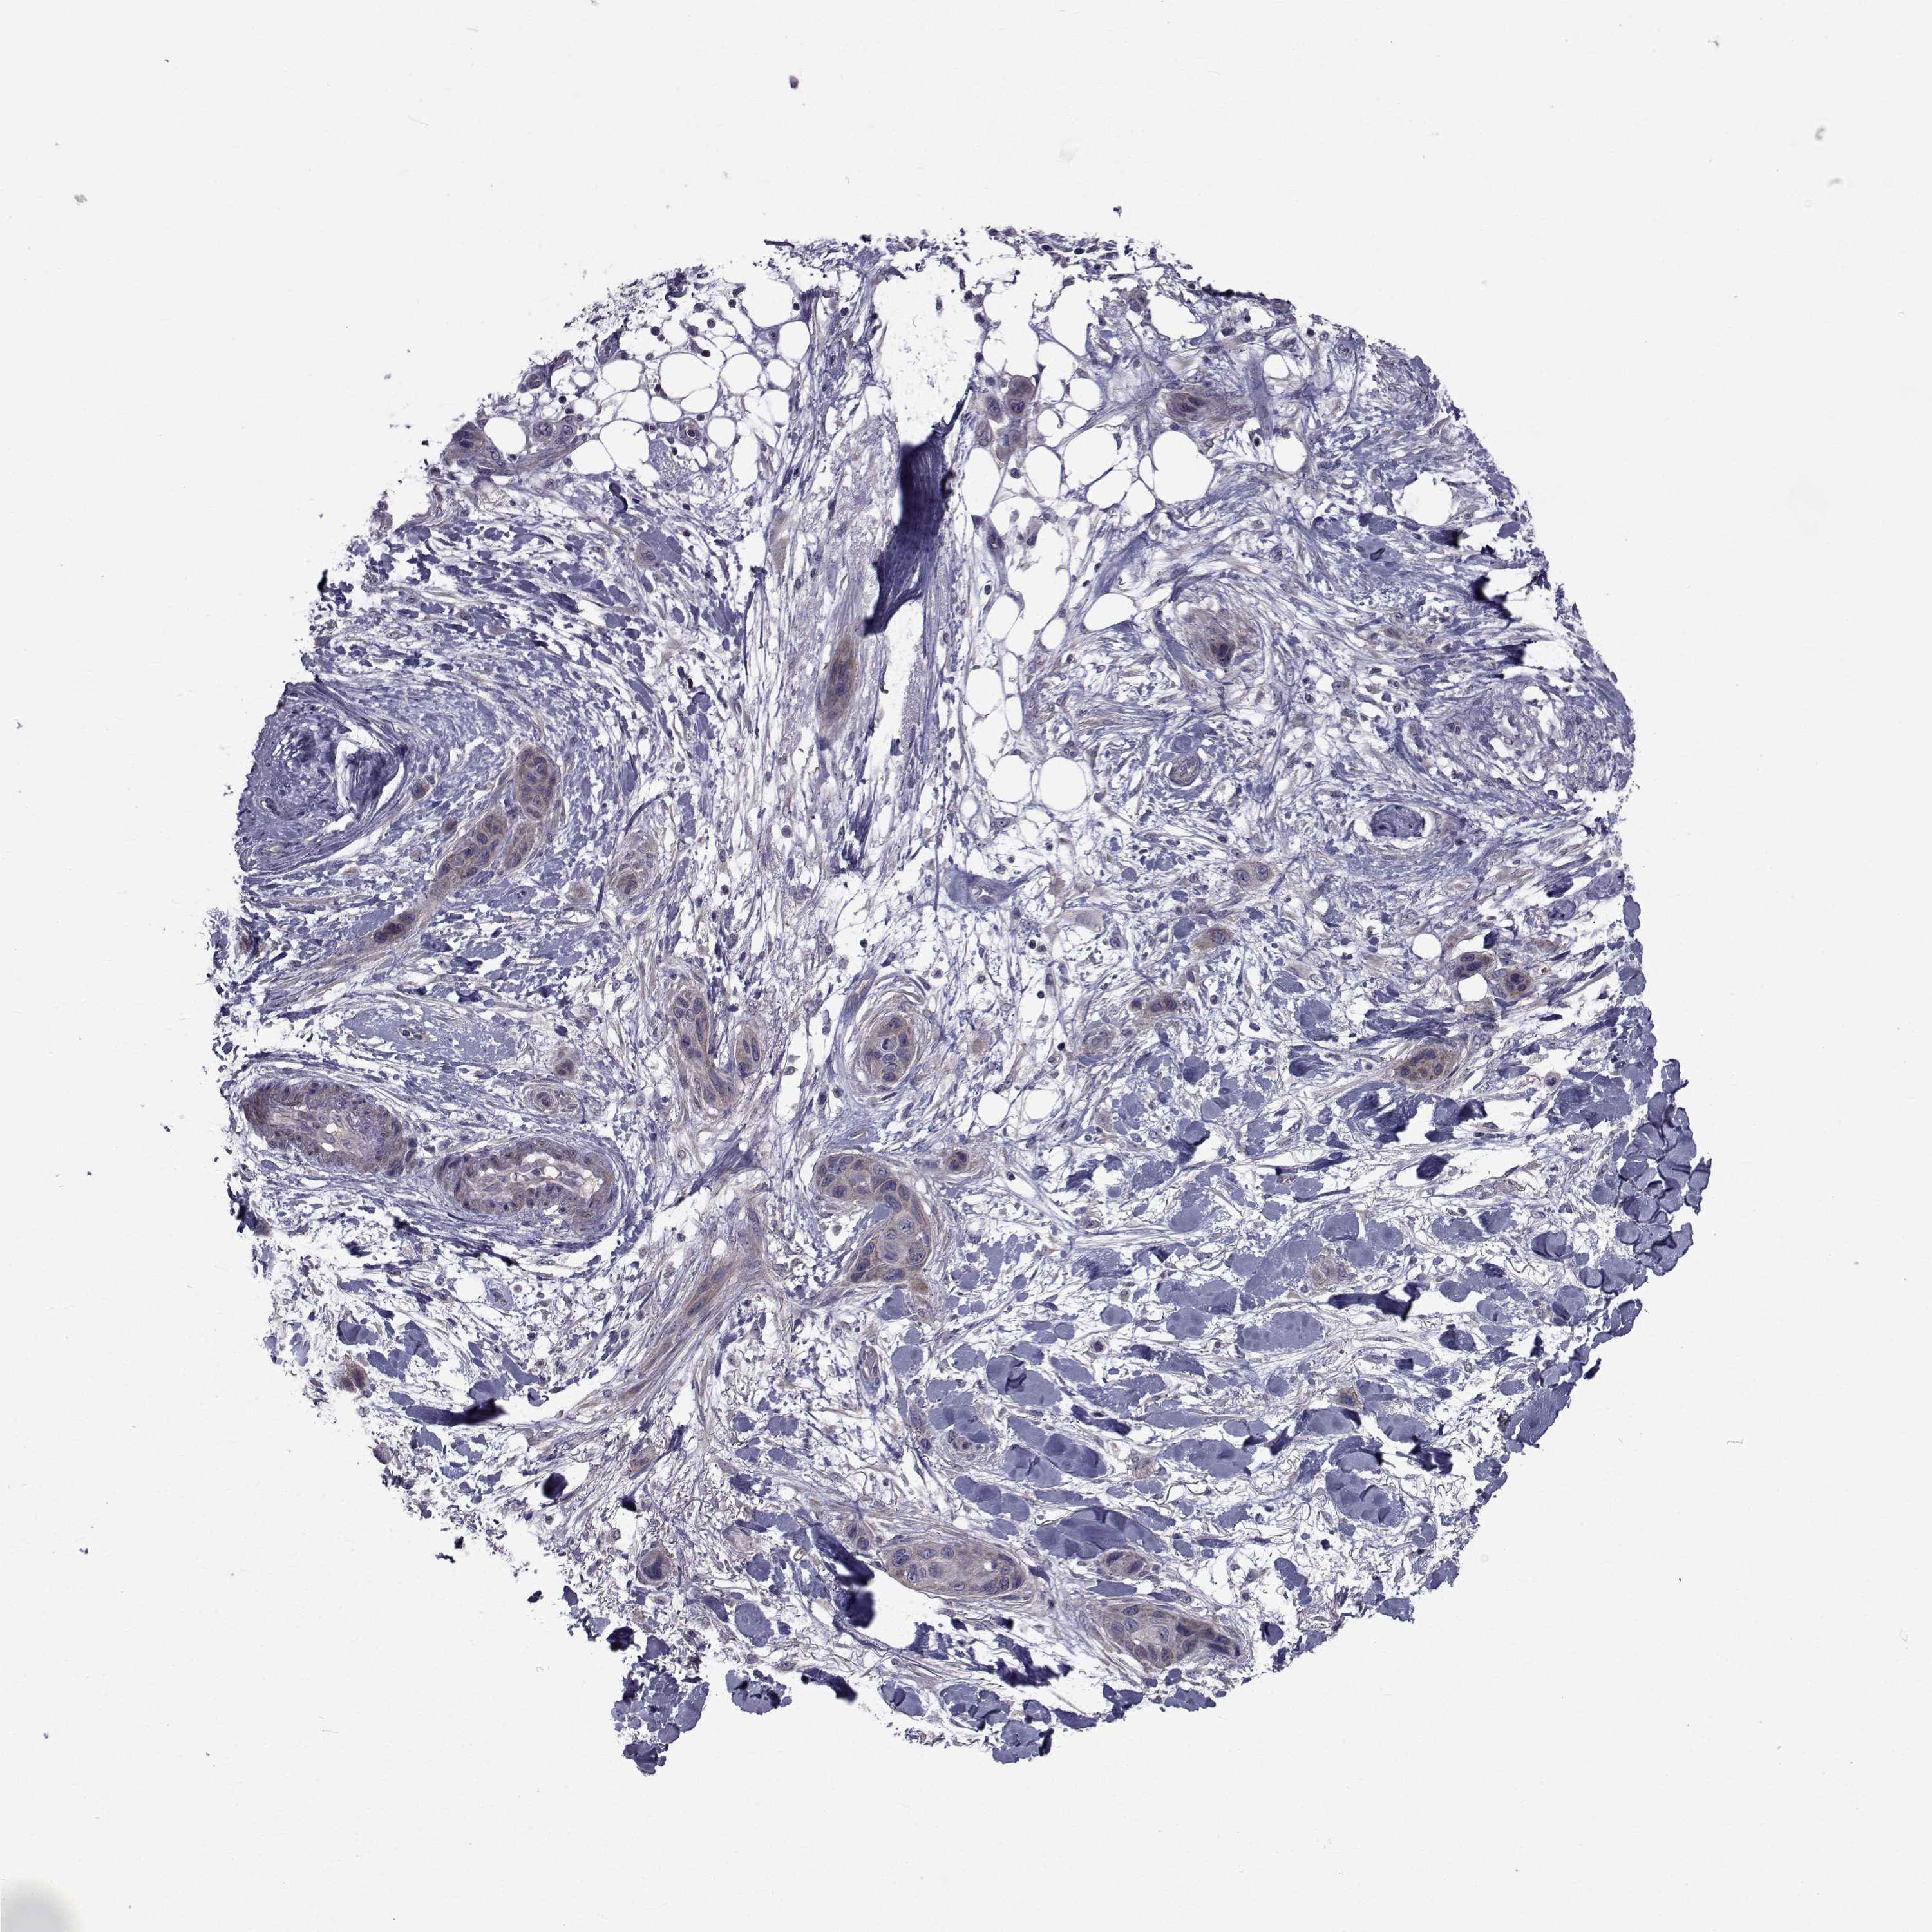

SKIN CANCER - Protein expressioni

A mouse-over function shows sample information and annotation data. Click on an image to view it in a full screen mode. Samples can be filtered based on level of antibody staining by selecting one or several of the following categories: high, medium, low and not detected. The assay and annotation is described here.

Each image is clickable and will lead to virtual microscopy that enables deeper exploration of all samples and also displays staining intensity scores, fraction scores and subcellular localization as well as patient and tissue information for each sample.

Antibody HPA028521

Antibody HPA029274

Antibody HPA030240

Staining

High

Medium

Low

Not detected

Intensity

Strong

Moderate

Weak

Negative

Quantity

>75%

75%-25%

<25%

None

Location

Nuclear

Cytoplasmic/membranous

Cytoplasmic/membranous,nuclear

Basal cell carcinoma

Squamous cell carcinoma, NOS